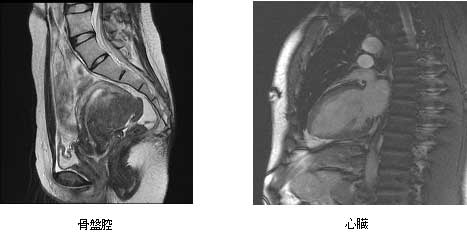

当クリニックでは、1.5T(テスラ)の高性能MRIシステム SIGNA Creatorを使用しています。

MRI検査とは強い磁石と特殊な電波の力により、人体内部の構造を鮮明に見ることができる医療用画像診断装置です。

その他、腹部領域、婦人科領域、泌尿器科領域の診断に対しても非常に有用ですので、検査希望や疑問点等ございましたら、ご気軽に医師、スタッフまでお声掛け下さい。